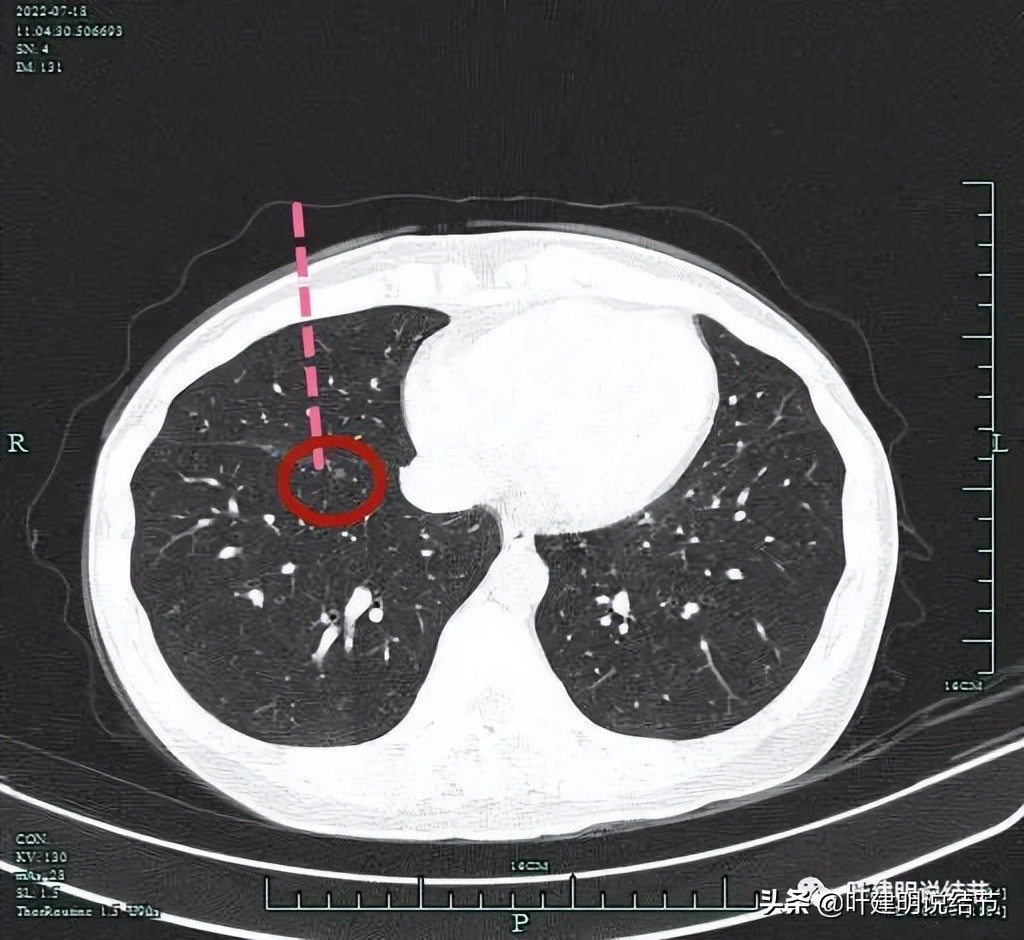

她的下叶还有一颗结节,虽然比较小,但密度也不是很淡,而且如果上叶的病灶要切除,同则这颗最好也切除,不然可能会在后续随访的3-5年内还要再次手术,但同样位置并不理想:

病灶虽然也是近斜裂处,但从胸壁进去的距离比较远,位置比较深,关键是同样它与下肺静脉之间的距离比较近,不足2厘米:

上图示病灶与下肺静静间的距离短。